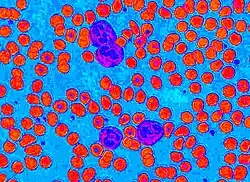

Circular thresholding is an algorithm for automatic image threshold selection in image processing. Most threshold selection algorithms assume that the values (e.g. intensities) lie on a linear scale. However, some quantities such as hue and orientation are a circular quantity, and therefore require circular thresholding algorithms. The example shows that the standard linear version of Otsu's method when applied to the hue channel of an image of blood cells fails to correctly segment the large white blood cells (leukocytes). In contrast the white blood cells are correctly segmented by the circular version of Otsu's method.